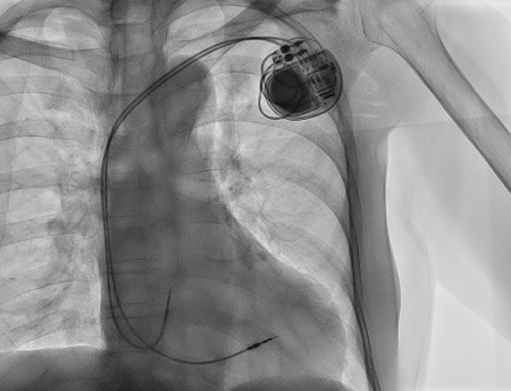

▼ ペースメーカ植え込み後の画像

洞不全症候群や房室ブロックという、脈が遅くなる疾患に対して、ペースメーカ植え込みを行っています。局所麻酔下に約1〜2時間程度の手術を行い、約1週間程度の入院での経過観察をおこなっています。

症例紹介

症例患者様:80代 女性

症例治療内容:完全房室ブロックに対して、恒久的ペースメーカー植込み

症例治療期間等:入院期間:7日間、手術時間:1時間20分、入退室:2時間、初回症例

※ 各循環器手術について(補足説明)